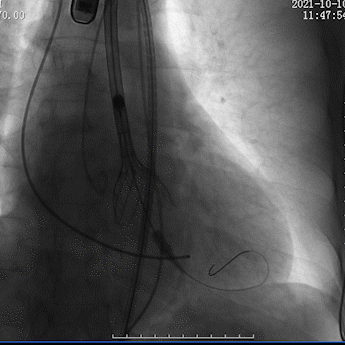

瓣膜释放至可回收极限处造影

瓣膜完全释放后造影